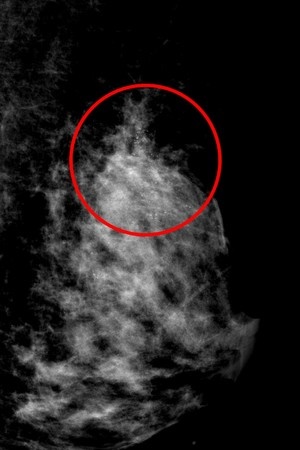

張群明主任說,乳房中的微小鈣化表現就如散沙一點一點散布或聚集在乳房中,在超音波上無法很明顯的照出來,得透過乳房攝影才能被發現,雖然乳房鈣化有八成為良性,但仍有少部分為惡性腫瘤的鈣化,需進一步取出乳房組織由病理科醫師判讀為良性還是惡性。

中、右圖:乳房醫學中心張群明主任說,乳房中的微小鈣化表現就如散沙一點一點散布或聚集在乳房中,在超音波上無法很明顯的照出來,得透過乳房攝影才能被發現。